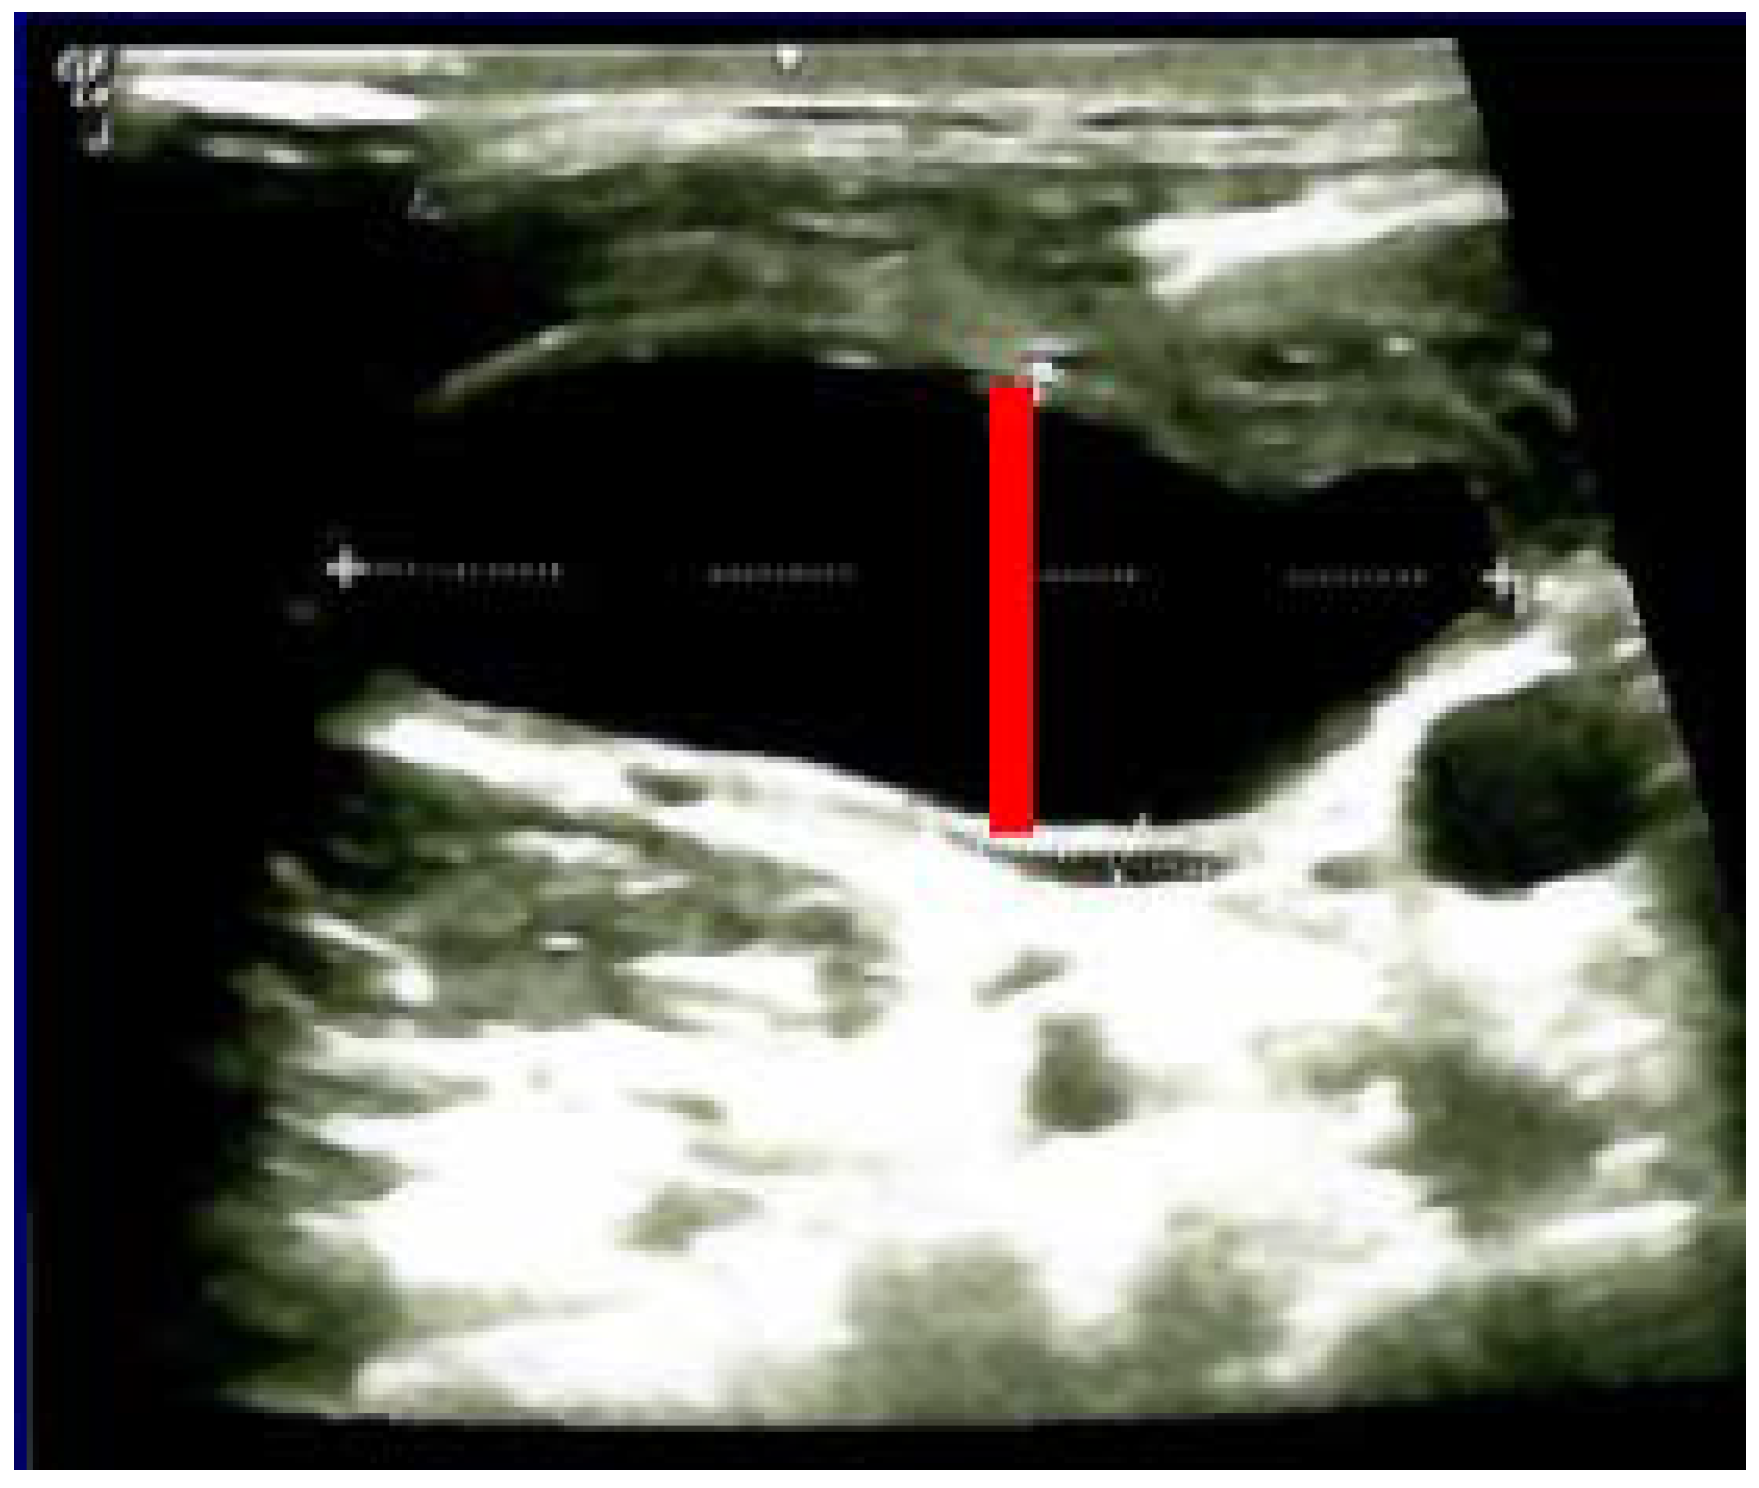

3.2. Thyroidectomy/Lymph Nodes Dissection and Lymphocele/Chylous Leakage

3.3. Post-Thyroidectomy HS and Lymphocele